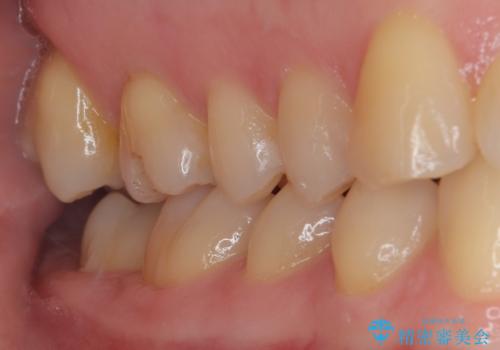

- 以前他院で治療した銀歯が外れてしまったとのことで来院された患者様です。

精査の結果、歯の神経は問題ないですが、欠損している範囲が大きいため部分的な詰め物では脱離や破折のリスクが高いため、オールセラミッククラウンによる補綴治療を行っていくこととしました。